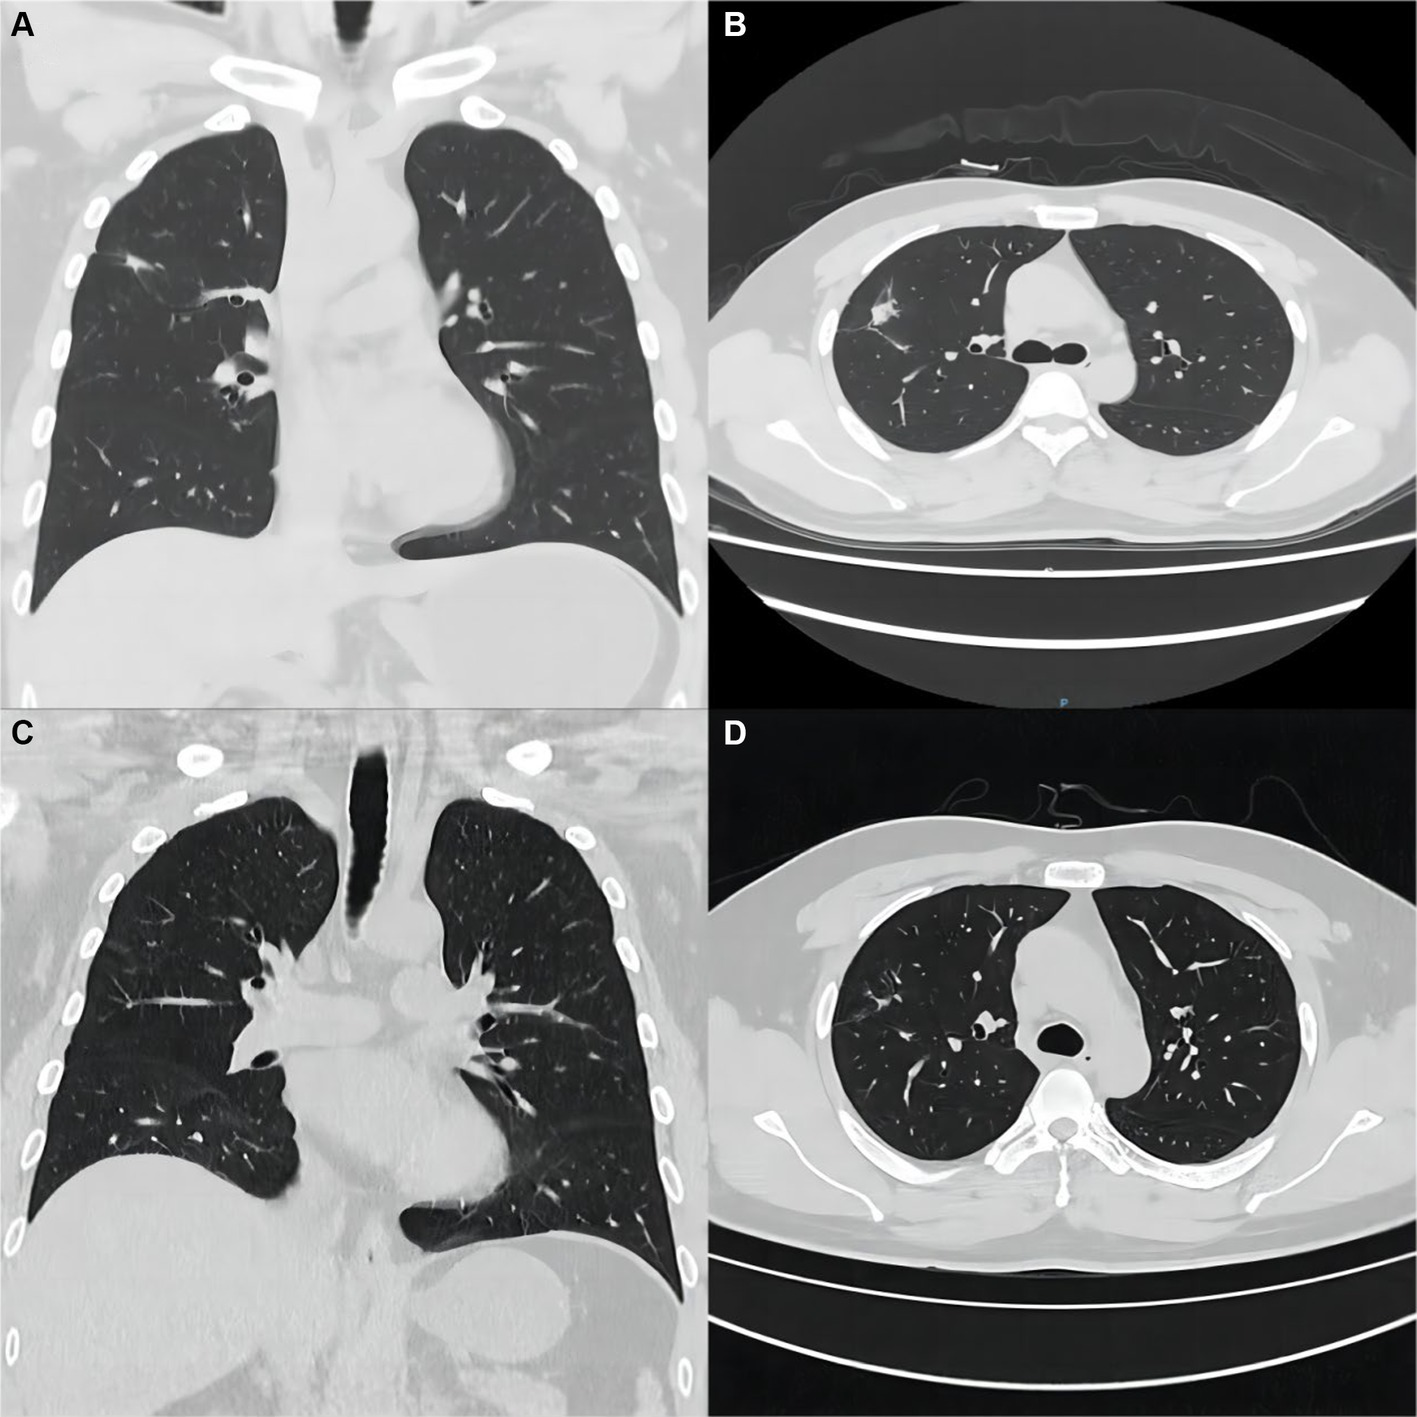

Blood and sputum pathogenic tests and an aspiration biopsy of the right lower lung lesion were done during hospitalization. Tests for bacteria, fungi, viruses, mycoplasma titer, and Legionella antigen were negative. Combining the clinical and special staining findings, we diagnosed the lesion of the lung as granulomatous inflammation (Figure 1D). Immunohistochemical results were as follows: TTF-1 (epithelial +), CK7 (epithelial +), CD68 (histiocyte +), ALK (−), and SMA (few +). Special staining results were as follows: antacid (−), PAS (−), and PASM (−). The special staining results are shown in Supplementary Figure S1. Bacterial, fungal, mycobacterial, and cytological analyses showed the absence of cancer cells and infection. These findings were consistent with the diagnosis of CD-associated granulomatous pneumonia. Based on the above judgment, the patient started immunomodulatory therapy with oral corticosteroids and azathioprine. CT scans 6 months after discharge showed significant improvement of the pulmonary lesions (Figures 2A,B), indicating that these were associated with CD. During the next 2+ years of follow-up, infliximab maintenance therapy was changed in 2021 for CD; follow-up has been stable to date. The patient’s pulmonary lesions remained asymptomatic, and a lung CT in May 2022 suggested focal fibrosis (Figures 2C,D).

Figure 2

Imaging and pathological findings of the patient at the time of return visit. (A,B) After 6 months of treatment, a repeat chest CT showed significant improvement of the original lung lesion. (C,D) CT scan of the chest at follow-up until May 2022, with only a few fibrous lesions remaining from the original lung lesion.